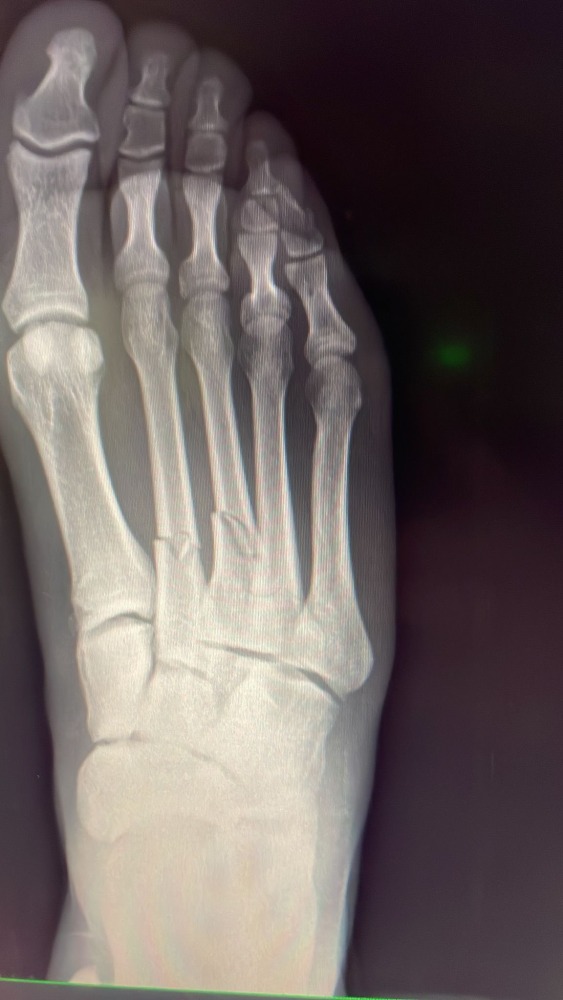

شارك كارلوس أكابو مدافع نادي قادش صورة لقدمه التي تعرضت للإصابة بعد تدخل من مهاجم ريال مدريد إيدين هازارد خلال المباراة التي جمعت بين الفريقين أمس الأحد.

وتعادل النادي الملكي مع مضيفه قادش 1-1 في مباراة أمس، وقبل نحو ربع ساعة من نهايتها خرج المدافع أكابو متأثر بإصابته بعد تدخل قوي من المهاجم البلجيكي.

ونشر أكابو عبر حسابه الشخصي في موقع تويتر صورة تظهر تعرض قدمه لإصابة قوية، وأرفقها بتعليق يتضمن رمزَيْ البطاقة الصفراء ووجه تعبيري مستنكر، في إشارة منه إلى استغرابه من حصول هازارد على البطاقة الصفراء فقط إثر تدخله العنيف.

وشارك أكابو صورة أخرى تظهر صورة أشعة لقدمه، مشيرا إلى تعرض عظم إصبعين للكسر، وقال إنه سيعمل من أجل التعافي من إصابته سريعا.